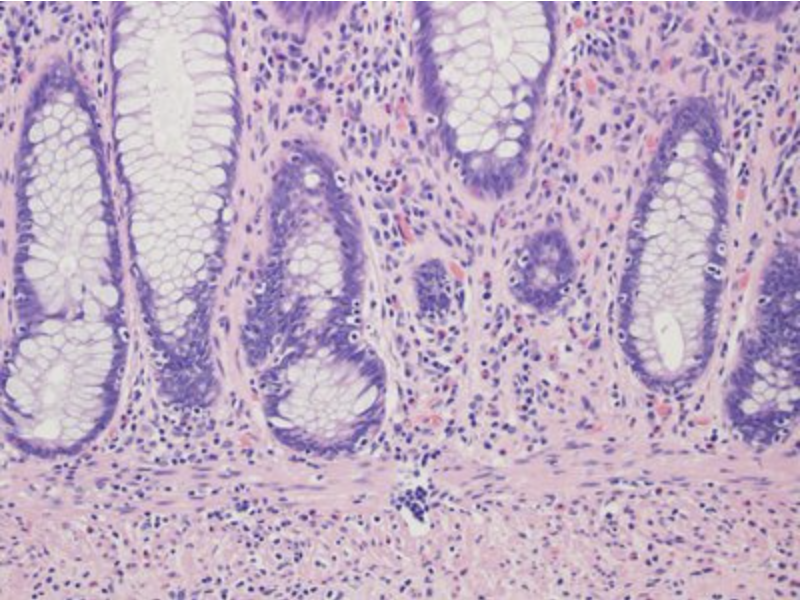

In this image, identify the structure that brings nutrients and oxygen to both the epithelial and connective tissues!

Most epithelia rest on connective tissue that contains the microvasculature bringing nutrients and oxygen to both tissues. Notice the red blood cells within these vessels.